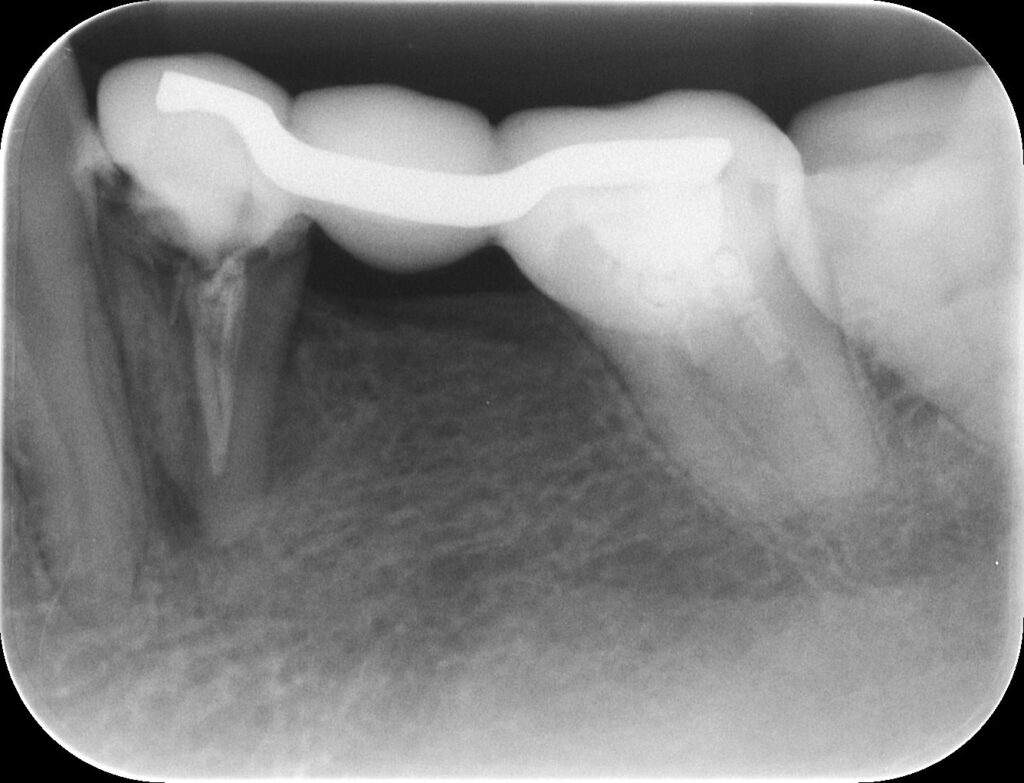

↑上記の写真は、ブリッジの土台の歯が破折し、歯が抜歯になった一例である

全ての症例がこのような未来になるわけではないが、リスクとしては上がってしまう。歯の欠損が多くなれば、さらに残った歯に負担がかかり、同じく歯の破折が起こるリスクがさらに上がってしまう。

適切な診断を行うためにレントゲン写真を撮影したところ、完全にブリッジの土台となる歯が破折していることが確認できました。

破折した歯は感染源となり、腫れや痛みの原因になる場合が多く、今回も痛みがあり、すでに感染が広がっていたので、患者様と相談の上、破折歯は抜歯を行うこととしました。